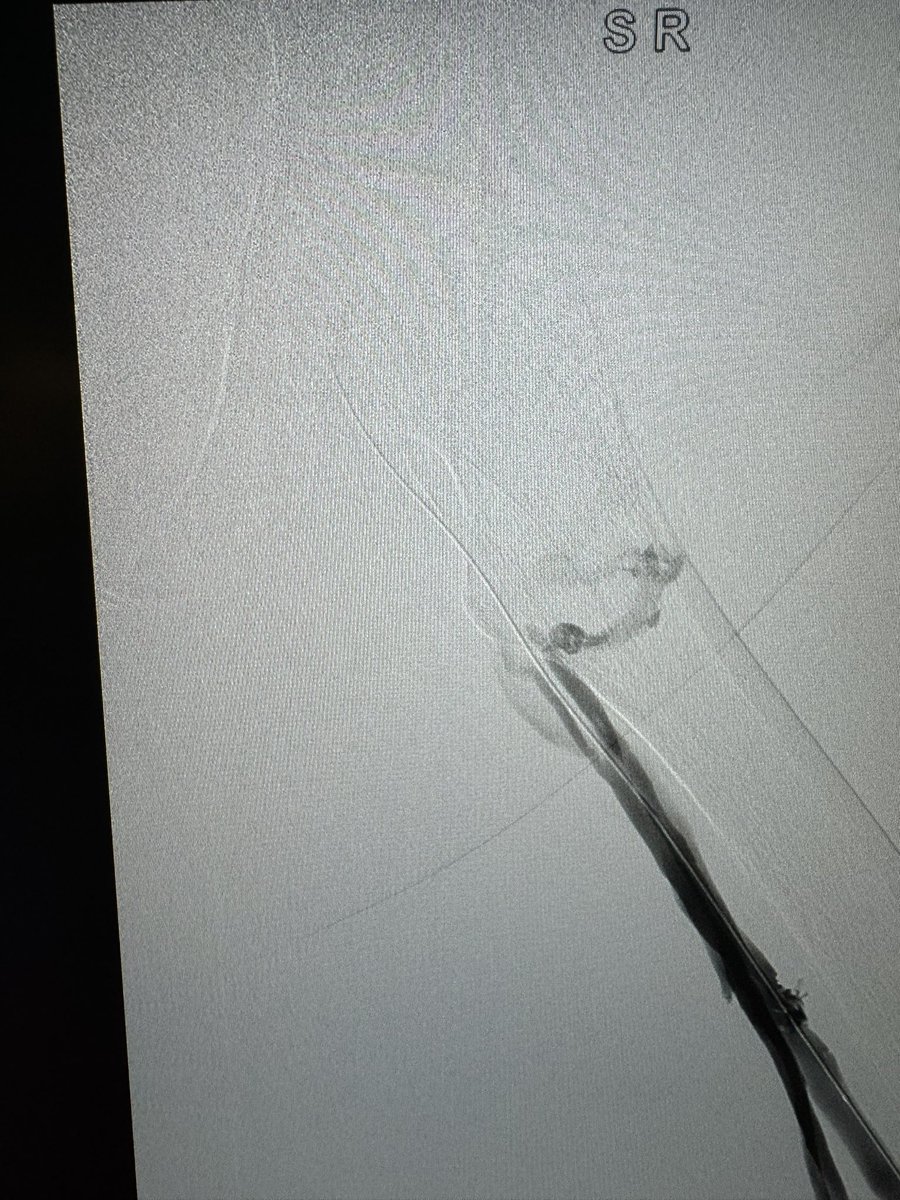

Acute limb femoral pop occlusion tx with 7f bolt Pneumbra . Super impressed .@PenVascular @jcgeorgemd